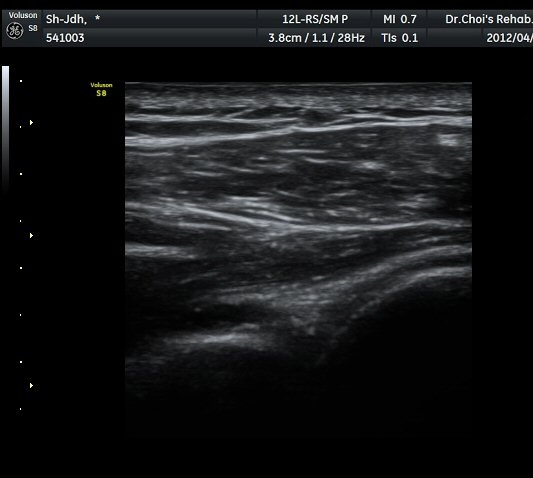

¾î±ú µÚ °üÀý¼ø °Ë»ç¿¡¼­ °üÀý¼ø Ç¥Ãþ¿¡ Àú¿¡ÄÚ ¼ö¾×Àú·ù°¡ °üÂûµÊ(»çÁø 4).

ŽÃËÀÚ¸¦ Á» ´õ µÚ·Î À̵¿ÇÏÀÚ °üÀý¼ø ³»Ãø °¡½Ã°üÀý¿À¸ñÆÐÀÓ(spinoglenoid notch)¿¡

¿øÇü¸ð¾çÀÇ Àú¿¡ÄÚ ³¶Á¾ÀÌ °üÂûµÊ(»çÁø 5, 6).

ÃÊÀ½ÆÄ °Ë»ç ; ³¶Á¾ÀÇ Å©±â°¡ Å©°Ô(1/5) ÁÙ¾îµë

ÈíÀÎ 5ÀÏ ÈÄ ³¶Á¾ÀÇ Å©±â